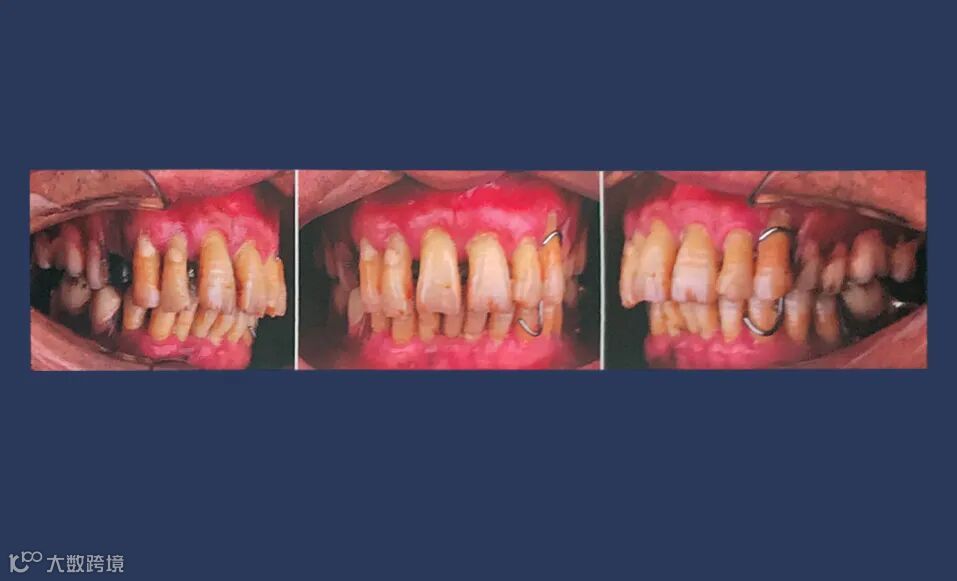

口外检查:面部对称无偏斜,面下1/3垂直高度正常,口角无偏斜,鼻唇沟加深,中线略偏右侧。低位笑线,前牙开唇露齿。开口度正常。

口内检查:13-23牙龈退缩,牙齿松动2-3度,14-17,24-27缺失,牙龈颜色质地正常,36、37、45、46、47缺失,下颌余留牙松动1-2度。

咬合检查:前牙深覆盖深覆he,后牙活动义齿咬合稳定。

牙周检查:上下颌牙周探诊深度均大于5mm,上颌余留牙松动2-3度。下颌余留牙松动1-2度,牙龈轻度水肿,探诊出血。